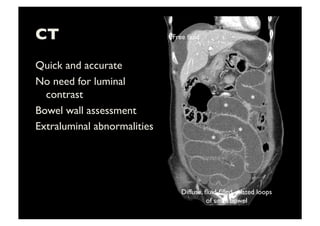

CT

Quick and accurate

No need for luminal

contrast

Bowel wall assessment

Extraluminal abnormalities

Diffuse, fluid-filled, dilated loops

of small bowel

Free fluid